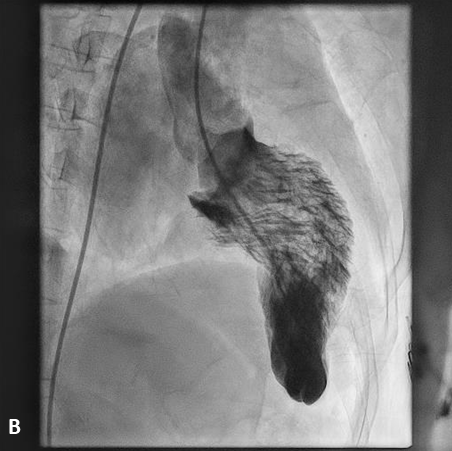

After obtaining informed consent, the patient was taken up for a left heart catheterization and coronary angiography to look for an appropriate septal branch for alcohol septal ablation. The left ventricular systolic pressure was significantly elevated (LVESP 250 mm Hg) and the left ventricle (LV)-to-aorta pullback showed an intracavitary gradient of 140 mm Hg, with no left ventricular outflow tract (LVOT)-to-aorta gradient. The LV angiogram showed the “ballerina foot deformity”, which represents the asymmetrical septal hypertrophy with LV hypercontractility; and severe mitral annular calcification with grade 3 mitral regurgitation (Figure, Videos 1 and 2). Her coronary angiography revealed a significant obstructive disease in the mid-left anterior descending artery (LAD), while the rest of the vessels were normal. After discussion with the heart team, she was taken up for alcohol septal ablation, which successfully decreased the LVOTO gradient to 25 mm Hg. Subsequently, percutaneous coronary angioplasty to the LAD was done successfully and the patient was discharged with significant symptomatic relief.

Ballerina foot appearance is a long-described LV angiography sign in hypertrophic obstructive cardiomyopathy that reflects LV hypercontractility with a resultant narrow LV systolic cavity, resembling a ballet dancer’s feet. The eponym has also been used to describe the appearance of basal LV hypercontractility and the visibly prolapsing leaflet on LV angiography in mitral valve prolapse syndrome.